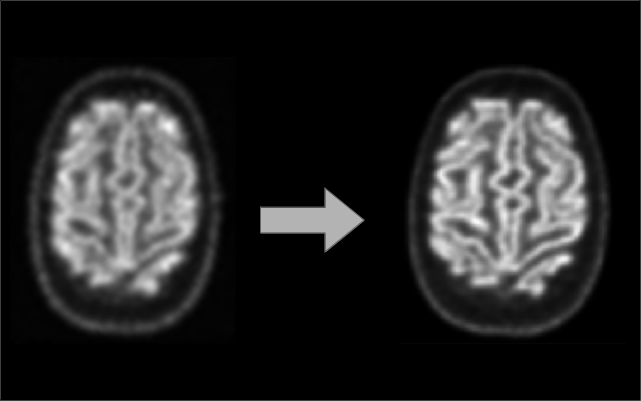

Gaussian Splatting-Based PET Image Correction Tool

Developed a proof-of-concept tool that enhances PET image correction using Gaussian splatting. This approach replaces traditional registration methods by utilizing Gaussian functions to represent corrected and uncorrected PET images, leading to improved accuracy in transmission-less PET imaging. (Published in IEEE MIC 2024)

I was responsible for creating the base pipeline, designing and implementing the framework using PyTorch, Pydicom, PIL, wandb